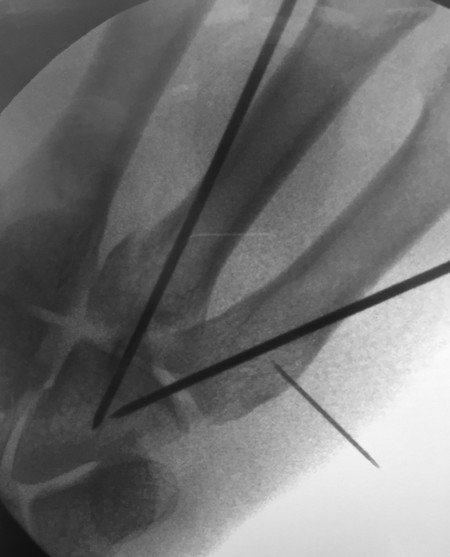

14.5 Fracture Dislocations of the Base of the Fourth and Fifth Metacarpals

These injuries can be easily missed and that is why it is essential to always examine three views (anteroposterior [AP], lateral, oblique) in the emergency department (Fig. 14‑10 a,b). They are inherently unstable and even after reduction under anesthesia the base of the fourth and fifth metacarpal will often re-dislocate even in a well-molded plaster cast.

The best approach is closed reduction and Kirschner wires going into the hamate bone from the fourth and fifth metacarpals (Fig. 14‑11). Rarely, it is necessary to open these fractures to achieve reduction.